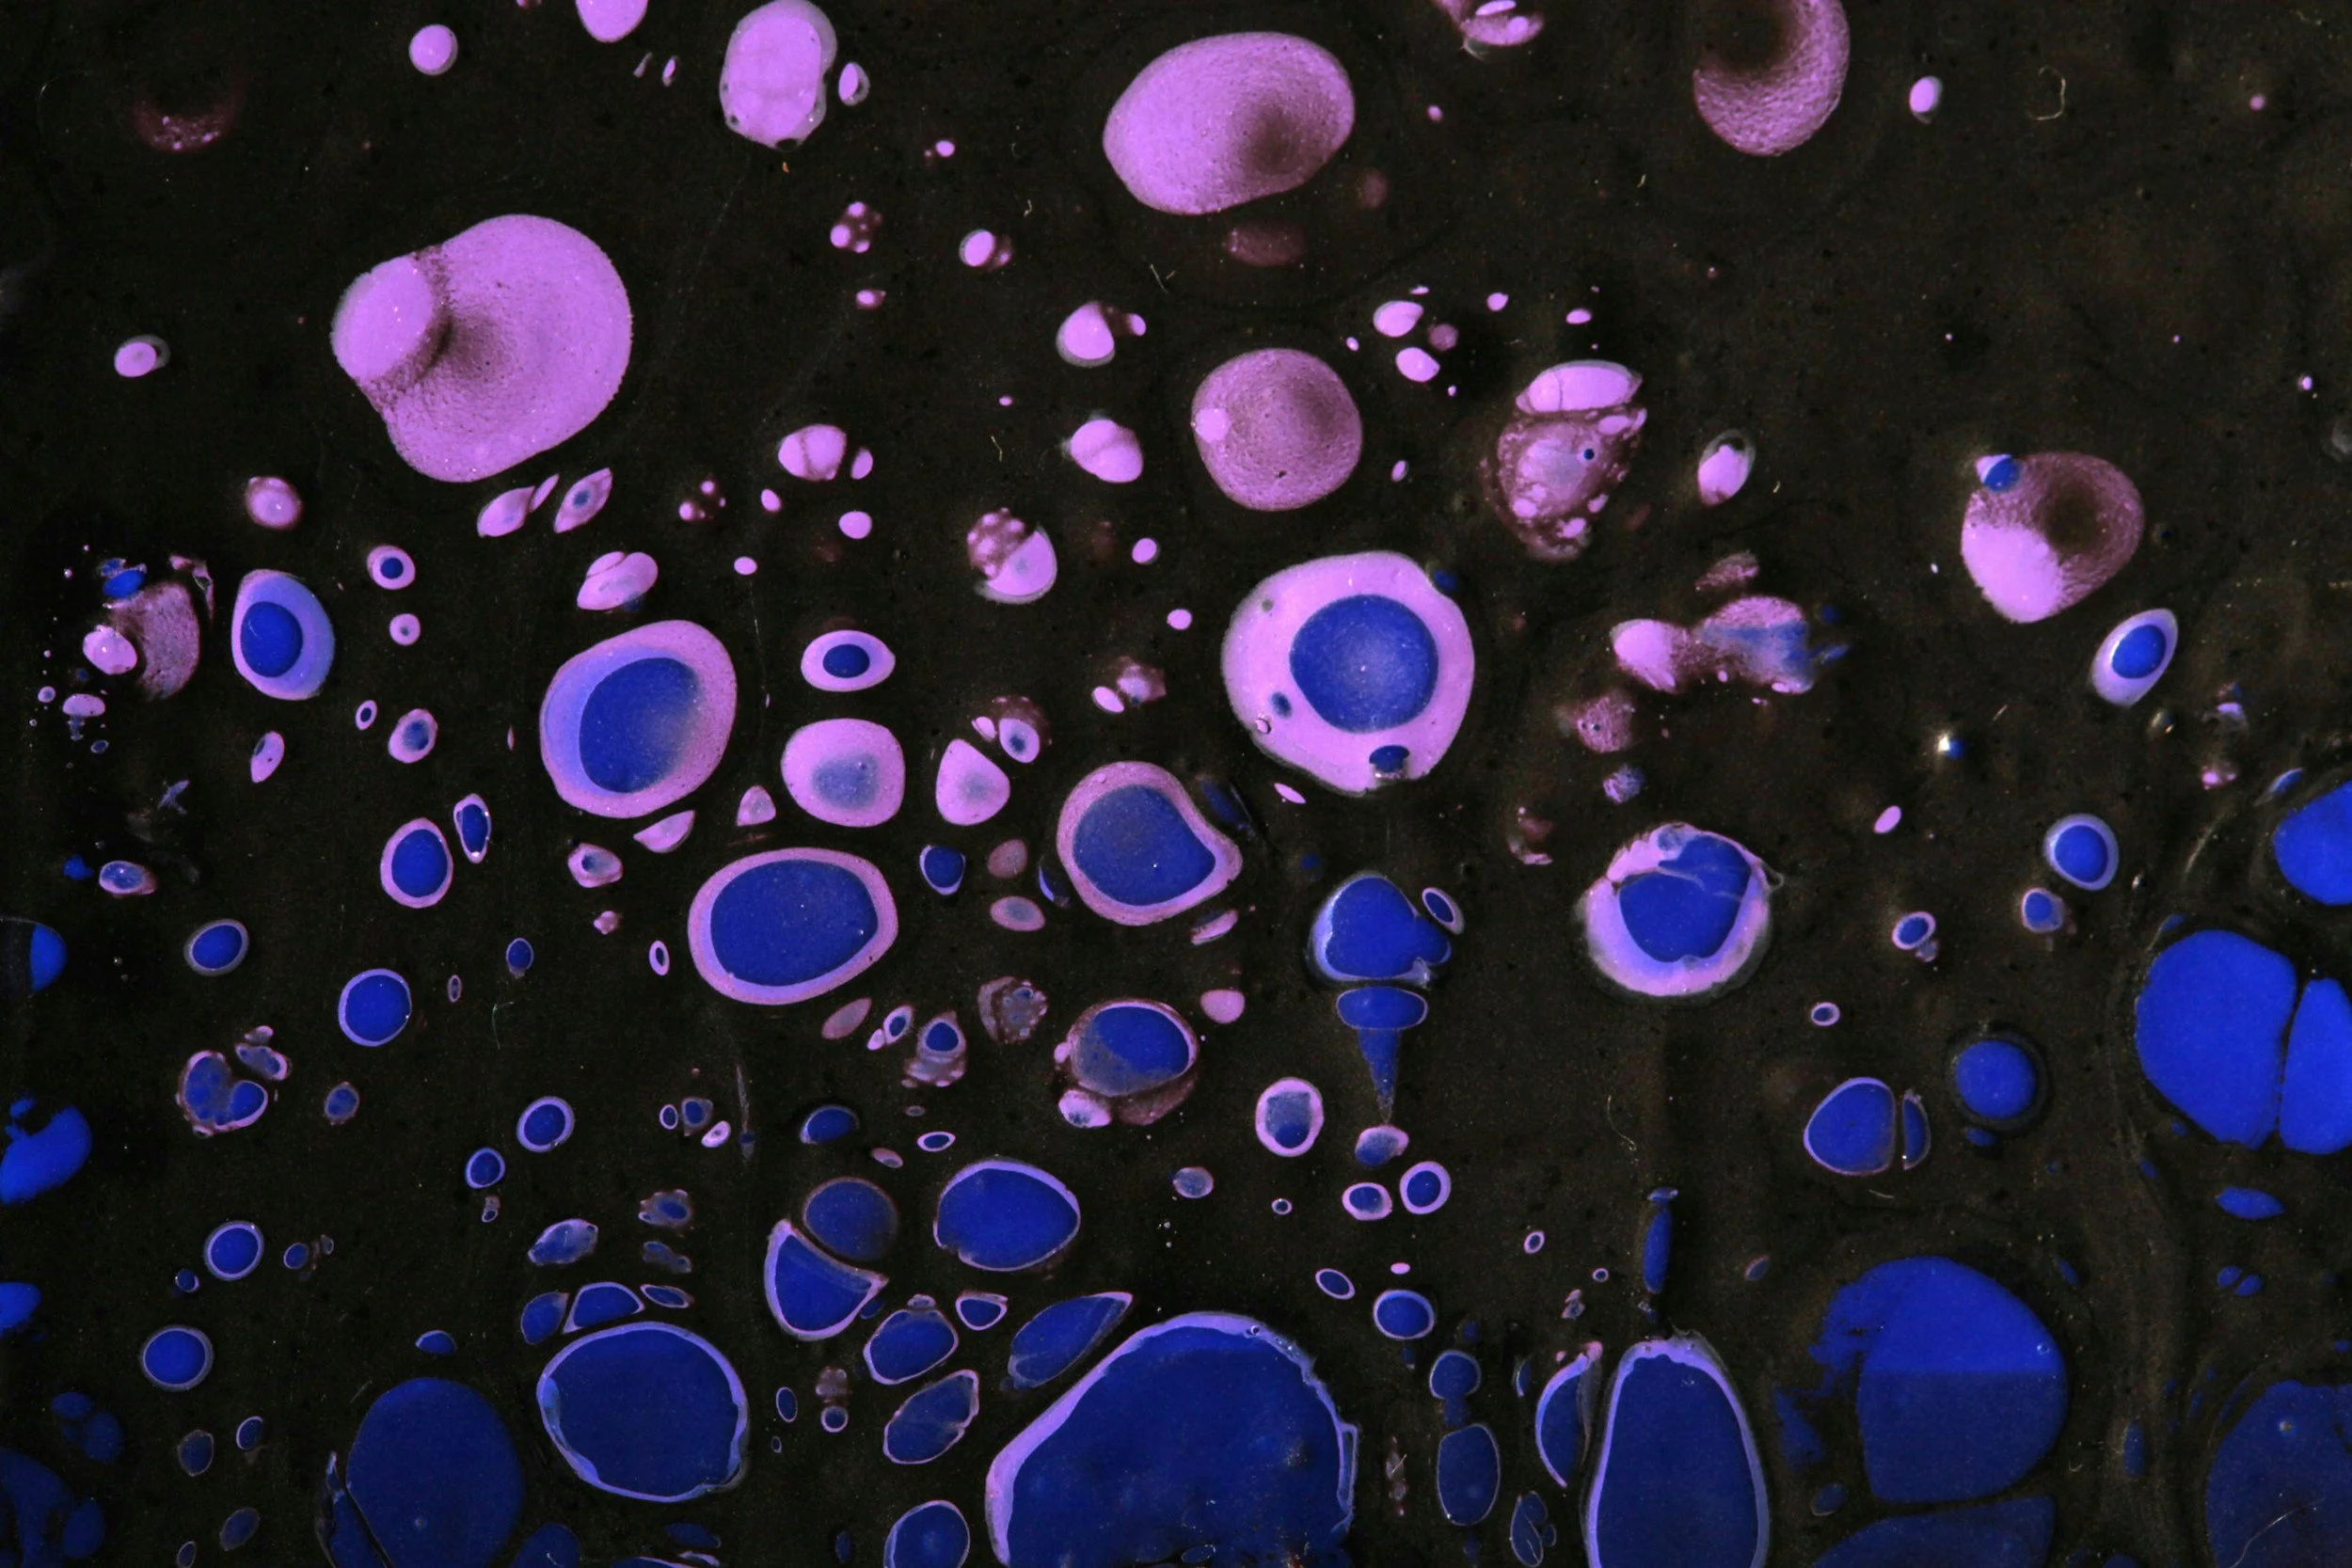

Exosomes are tiny, biologically active vesicles released by stem cells and other cell types. They act as messengers, carrying proteins, lipids, and RNA molecules that help coordinate tissue repair, inflammation modulation, and immune system regulation.

Stem cells are specialized cells with the ability to repair and regenerate damaged tissues. We use umbilical cord–derived stem cells, which are non-manipulated, ethically sourced, and processed in FDA-registered, AABB- and AATB-accredited facilities.